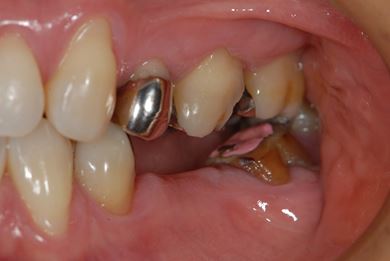

| 主訴 | ブリッジの支えとなっている歯が虫歯になり、ブリッジが難しくなったため、インプラントか義歯かの相談で来院。 | ||||||||||||||||||||||||||||||||

| 治療方針 | 抜歯と同時にインプラント治療を行い、治療期間を短縮する。 | ||||||||||||||||||||||||||||||||

| 治療内容 | インプラント4本(抜歯即日スピードインプラント治療)、ハイブリッドセラミッククラウン6本 | ||||||||||||||||||||||||||||||||